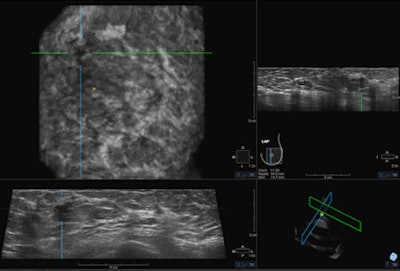

Last September the U.S. Food and Drug Administration (FDA) approved the somo-v ABUS device for use in combination with mammography in women with dense breast tissue. This may drive increased interest from physicians in the use of ultrasound as a screening tool. Image courtesy of GE Healthcare."This study actually demonstrates a 57% rise in finding breast cancer compared to the overall statistics for the year before," she told AuntMinnieEurope.com. "Together with studies in the United States, this study shows that adding ABUS to mammography finds 50% more cancers in the screening program, and more importantly, the cancers would be found when smaller and at an earlier stage."

The somo-v ABUS system was specifically designed not only for screening dense breast tissue, but also to operate efficiently in the screening environment. Being automated in nature, the device is operator independent and is associated with enhanced consistency, and the radiologist only needs to interpret the images rather than necessarily conducting the scan, aiding workflow, and managing time efficiency, she explained.